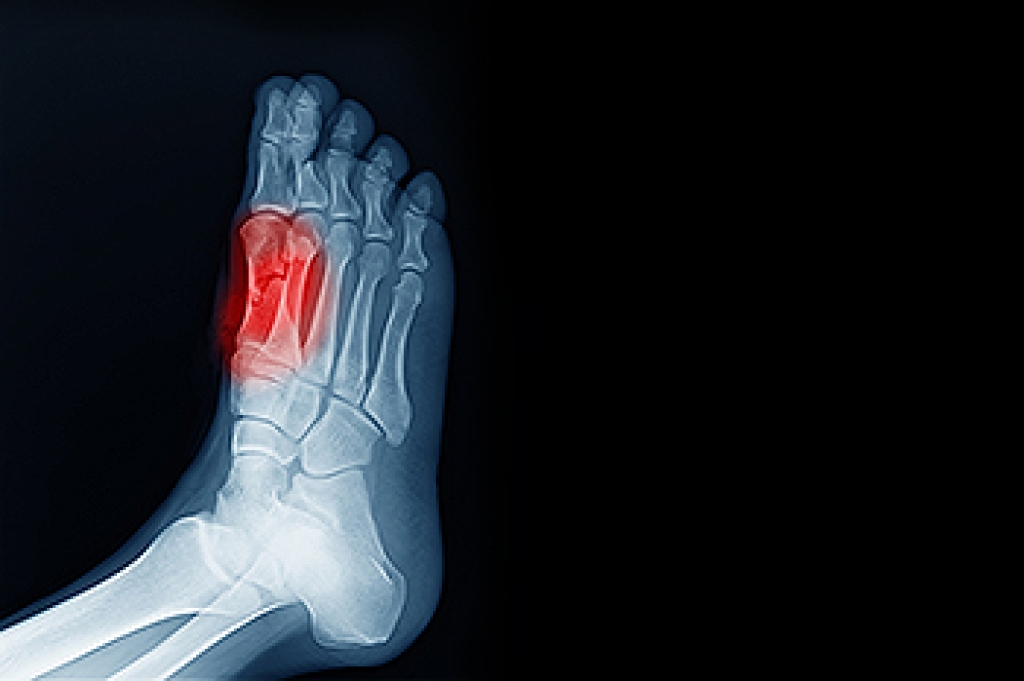

In many cases the cause of toe pain is obvious, but in others, a podiatrist may want to use more advanced methods to determine the problem. These can range from simple visual inspections and sensation tests to X-rays and MRI scans. Prior medical history, family medical history, and any recent physical traumatic events will all be taken into consideration for a proper diagnosis.

- Fractures (broken bones)